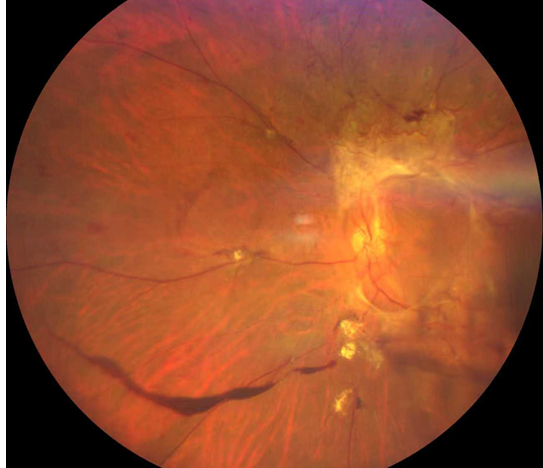

廈門眼科中心的檢查結(jié)果讓全家倒吸一口涼氣:

右眼視力0.05,左眼僅余眼前光感;

雙眼被確診為Ⅱ期增殖性糖尿病視網(wǎng)膜病變(以下簡稱“糖網(wǎng)”),并伴有黃斑水腫。

糖尿病視網(wǎng)膜病變

這意味著,如果再晚來幾天,視網(wǎng)膜損傷將不可逆轉(zhuǎn),他將永遠(yuǎn)失去光明。

萬幸,眼底病科王曉波主任為鄭先生實(shí)施了左眼25G微創(chuàng)萬速玻璃體切割手術(shù)聯(lián)合抗VEGF藥物注射治療,手術(shù)很順利。術(shù)后鄭先生左眼視力逐漸恢復(fù)到0.5。